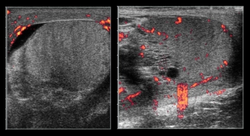

Normal Testicle

- Equal heterogeneity

- Equal blood flow

- Minimal fluid around the testicle

Testicular Torsion

- Enlarged testicle

- Increased heterogeneity

- Decreased flow on power Doppler

- Increased flow may be seen in cases of torsion with subsequent detorsion

Normal